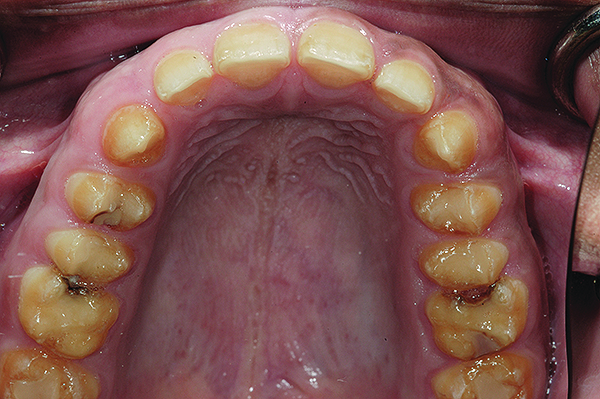

Figure 6. Preoperative maxillary occlusal view.

Figure 6

A thorough clinical examination and analysis were carried out to assess the esthetic and functional problems of the patient (Figure 2 through Figure 7). The medical history was non-contributory, except for mild leukoderma. Temporomandibular joint (TMJ) function was within normal range.

Mounted study casts were used to evaluate occlusion. The relevant findings were as follows2: Facial analysis revealed a canted maxillary occlusal plane and canted dental midline. Dentolabial analysis showed that the maxillary incisors were not adequately visible during repose; it also revealed a reverse smile line, as well as a wide smile showing 12 teeth. Results from the phonetic analysis were that “F” and “V” sounds revealed upper incisal shortening, “M” and “S” pronunciation disclosed a diminished vertical dimension of occlusion (VDO), and “E” sounds showed severe shortening of incisors. Dental analysis revealed thick biotype, asymmetry and inappropriate location of gingival levels and zenith, incorrect axial inclinations, a displeasing width-to-length ratio, and pitted surfaces on most teeth. Interproximal decay was evident on several posterior teeth, as revealed by radiographic analysis. Finally, occlusal examination indicated discrepancy between maximum intercuspation (MIP) and centric relation (CR) as well as a lack of anterior guidance/posterior disclusion.